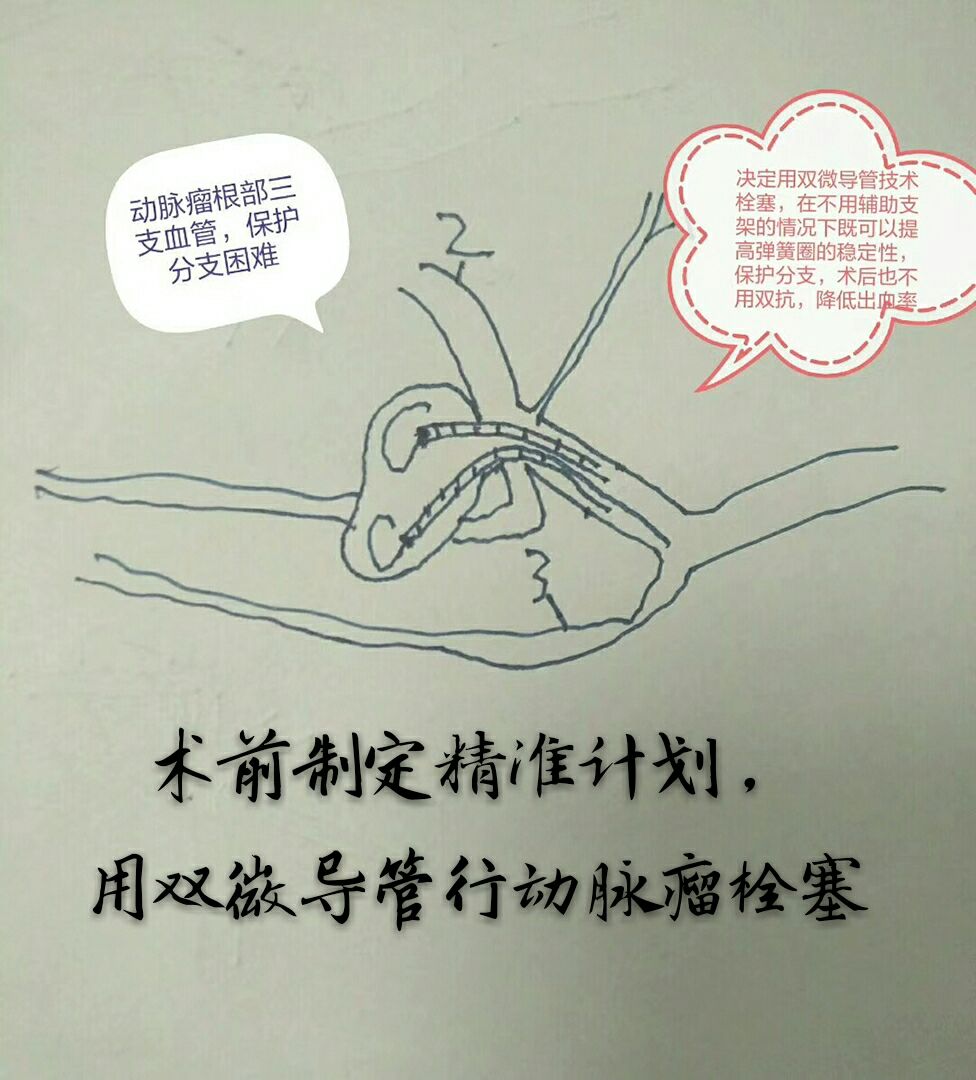

因瘤颈下方分支与动脉瘤关系密切,角度刁钻,而血管纤细,无法用辅助支架保护,术前做了详细、精准的计划,决定用双微导管技术栓塞

双微导管交替成栏栓塞,利用弹簧圈之间互相缠绕稳定弹簧圈